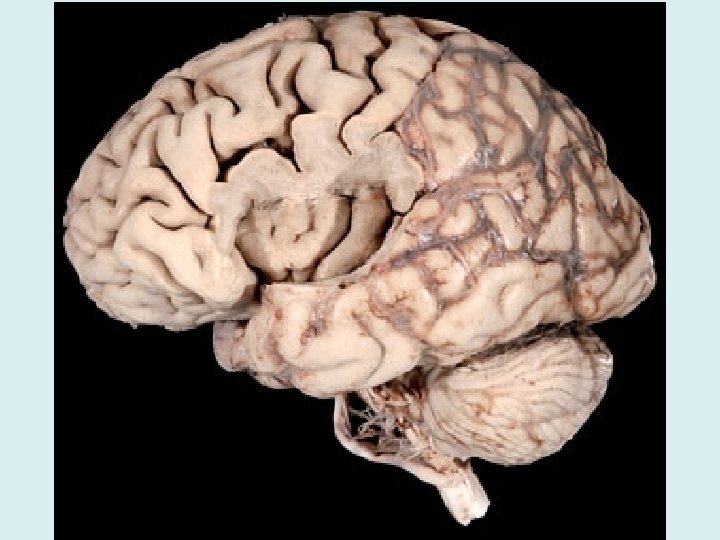

Brain Characteristics • Gyri: elevated ridges of tissue (gyrus is singular) • Sulci: shallow grooves separating gyri (sulcus is singular) • Fissures: deep grooves separating large regions of brain • Lobes: separations of hemispheres of brain

Senses & Controls of Brain - Cerebrum • White matter: collections of myelinated nerve fibers, usually found in deeper brain matter; carries the impulses (axons) • Gray matter: collections of UNmyelinated nerve fibers and cell bodies; usually found in the outer areas; contains the neuron cell bodies

Cerebrum • The cerebrum is divided into right and left hemispheres by the longitudinal fissure • Controls consciousness • Senses and motor control occurs here! • Each hemisphere divided into 4 lobes